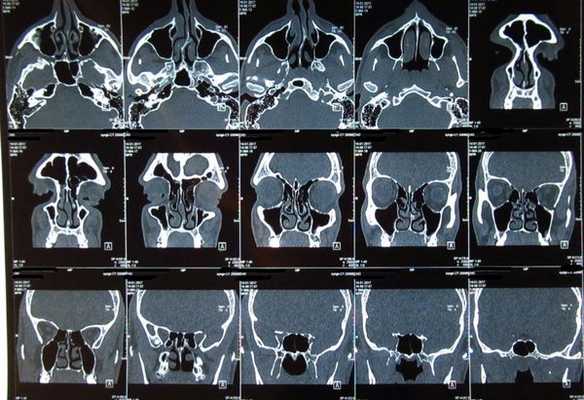

Классическое рентгенологическое исследование предусматривало выполнение рентгенографии в стандартных и дополнительных проекциях. КТ околоносовых пазух проводилось в двух взаимно перпендикулярных проекциях - аксиальной и фронтальной. Исследование в аксиальной проекции выполняли в положении пациента на спине, голову фиксировали подголовником. Плоскость сканирования выбирали по боковой топограмме параллельно твердому небу. Фронтальную проекцию выполняли в положении пациента на животе. Плоскость сканирования должна быть по возможности перпендикулярной аксиальной (это зависит от возможного угла наклона Гентри). Особенно важно соблюдать эти условия при повторных исследованиях для оценки динамики патологических изменений в процессе лечения. КТ околоносовых пазух полости носа и верхней челюсти проведено на аппаратах IV поколения "Sonatom Plus 4" и "Ar-Star" (Simens).

Исследовать околоносовые пазухи можно как в пошаговом режиме, так и в режиме спирального сканирования. Стандартно околоносовые пазухи исследуют в режиме спирального сканирования 3/4.5 мм или 5/7 мм с реконструкцией изображений 2-4 мм. При шаговом режиме исследования используют слой и шаг 2-5 мм в зависимости от конкретной задачи с использованием "мягкотканого и костного окна". Для более четкой оценки распространенности процесса, отграничения мягкотканного образования, перифокального отека и постлучевых изменений применяли контрастное внутривенное усиление йодсодержащими препаратами (омнипак).

- КТ и МРТ являются взаимно дополняющими методами диагностики опухолей полости носа и околоносовых пазух. КТ является методом выбора для оценки костных структур, наличия обызвествления, но возможности ее ограничены при дифференциальной диагностике опухоли от мягких тканей и реактивных изменений в пазухах. Внутривенное введение контрастного йодсодержащего препарата повышает диагностические возможности КТ. Опухолевые массы неравномерно накапливают контрастный препарат, и визуализация их улучшается на фоне реактивного экссудата.

- При МРТ лучше дифференцируется опухоль, реактивный выпот и отек слизистой, что позволяет более точно определить размеры опухоли и ее распространенность. Применение внутривенного усиления при КТ и МРТ улучшает оценку размеров, визуализацию структуры и границ опухоли, а также размеров внутричерепного компонента.